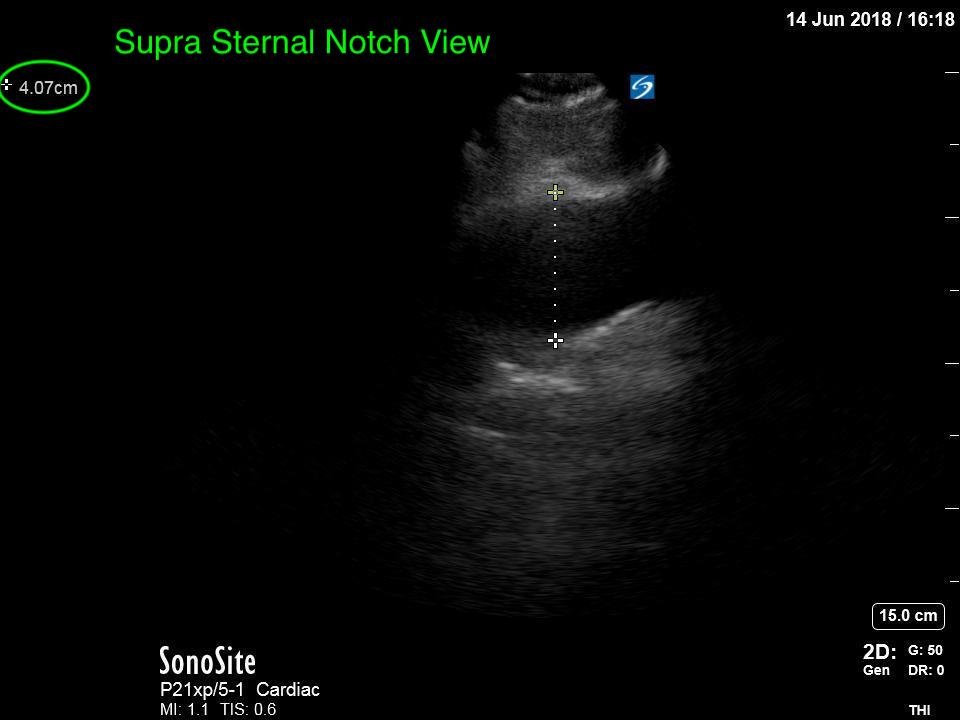

Thoracic Aortic Aneurysm Measured by Point of Care Ultrasound Suprasternal Notch View

Point-of-care cardiac echocardiogram demonstrated a dilated ascending aorta (illustrated in red) measuring approximately 4 cm in the parasternal long axis (PLAX). A dilated aortic arch (illustrated in green) also measuring approximately 4 cm was appreciated using the suprasternal notch view (SSNV). A follow-up computed tomography angiogram (CTA) was performed, validating bedside ultrasound measurements.

The diagnostic criteria for dilated thoracic aneurysm is based on multiple factors including age, sex, and body size.2 An aortic root diameter of ³ 4.0 cm constitutes an ascending aortic dilation.3,4 Point-of-care cardiac and SSNV ultrasound of the thoracic aorta has been validated as an accurate study when performed by emergency physicians to identify thoracic aortic aneurysms (sensitivity of 71.4%, specificity of 100% when compared to gold standard of CTA). 5 This case is an example of the utility of rapid bedside diagnostic ultrasound, specifically the SSNV, in assessment of thoracic aneurysms.

Point-of-care cardiac echocardiography demonstrated a dilated ascending aorta. Finding a new thoracic aortic aneurysm in the setting of chest pain and hypertension is a “can’t miss” diagnosis due to the potential for rapid expansion leading to dissection and/or rupture.6 Point-of-care ultrasound utilizing the SSNV is a tool that can be used early in the evaluation of the patient that can help make quick determination of diagnostic plan and expedite initiating treatment in the emergency department.